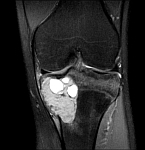

• Tumor surgery of the musculoskeletal system

• Resection of benign and malignant tumors of the bone and soft tissue

• Reconstruction of bone defects by biological procedures (from spongiosaplasty to bone transfer)

• Tumor total endoprosthesis (TEP) of all large joints and bones